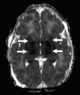

Hypoxic ischemic injury

Cerebral hypoxia is a form of hypoxia (reduced supply of oxygen), specifically involving the brain; when the brain is completely deprived of oxygen, it is called cerebral anoxia. There are four categories of cerebral hypoxia; they are, in order of severity: diffuse cerebral hypoxia (DCH), focal cerebral ischemia, cerebral infarction, and global cerebral ischemia. [Source: Wikipedia ]